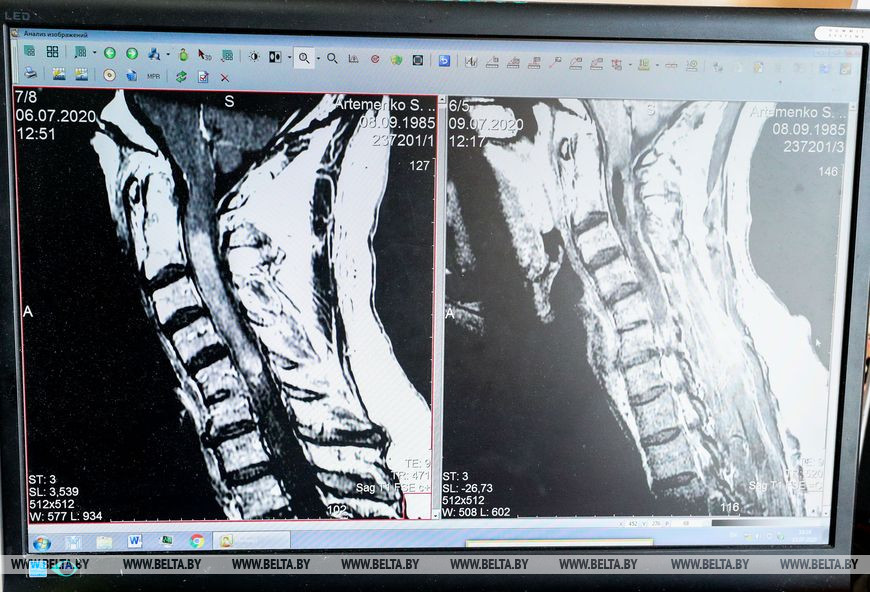

14 июля, Минск /Корр. БЕЛТА/. Белорусские медики провели сверхсложную операцию у пациента с опухолью внутри спинного мозга, сообщил журналистам ведущий научный сотрудник нейрохирургического отдела Республиканского научно-практического центра неврологии и нейрохирургии, кандидат медицинских наук Александр Головко, передает корреспондент БЕЛТА.

"К нам обратился гражданин Украины с опухолью внутри спинного мозга. Это достаточно редкая патология, которая занимает около 5-10% от всех опухолей спинного мозга. В Беларуси в год оперируют примерно 10-15 таких пациентов. Ситуация осложнялась тем, что опухоль имела достаточно большие размеры и располагалась в шейном отделе спинного мозга на протяжении трех позвонков. Сверхсложность таких вмешательств обусловлена высоким риском развития инвалидизации в послеоперационный период. Целью хирургического лечения таких пациентов является максимально полное удаление опухолей с сохранением функционально приемлемого статуса в послеоперационный период, то есть, образно говоря, чтобы человек мог себя обслуживать", - сказал Александр Головко.

По его словам, это действительно очень сложная операция. "Возможность выполнения таких вмешательств мы получили только с открытием РНПЦ и его оснащением соответствующим оборудованием и микроинструментарием. Такие операции длятся от 4 до 7 часов, в зависимости от обширности поражения. Серьезность операции обусловлена ее прогнозом. Зачастую, в зависимости от гистологического строения опухоли, она может не только сдавливать спинной мозг, но и разрушать его проводящие пути. Поэтому иногда во время операции приходится решать очень непростые вопросы на предмет радикальности удаления. Именно радикальное удаление позволяет излечить пациента от заболевания и дает наибольшие шансы для его последующего функционального восстановления", - отметил ведущий научный сотрудник.